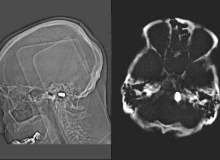

Beyin Felci Tipleri Nelerdir?

Nörolojik olan veya olmayan her hastalıkta olduğu gibi, beyin felcinde de bir sınıflandırma vardır. Bu sınıflandırmanın çeşitli nedenleri vardır. Öncelikle, sorunun altta yatan nedeninin şiddetini, bununla mücadele etme yeteneğini, tedavide başvurula